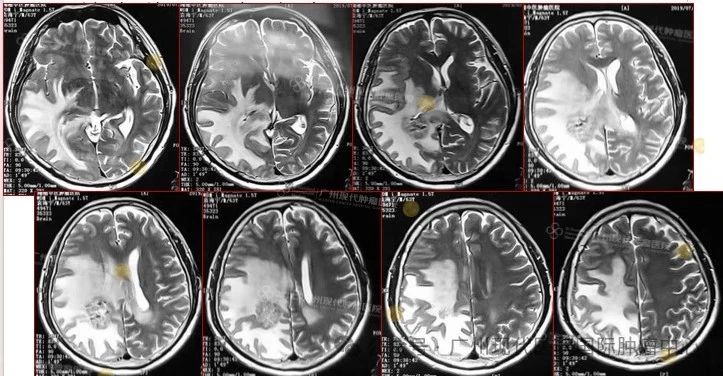

2019-7,颅内肿瘤基本消失,正常生活至今

2019年7月,颅内肿瘤已基本消失